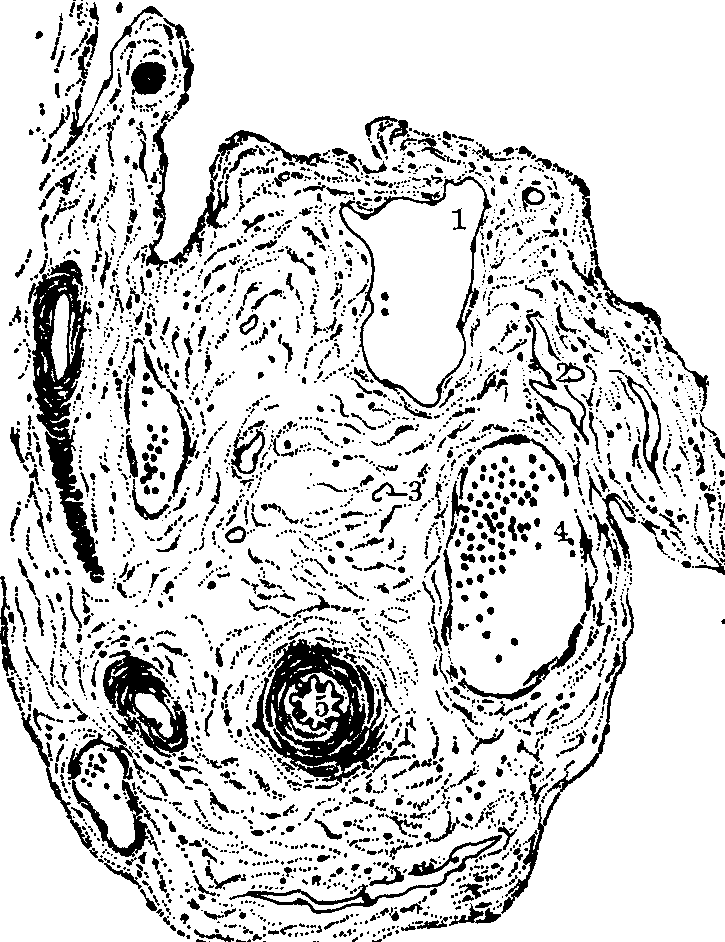

图1 大动脉结构(低倍光镜)

1.内皮 2.内皮下层 3.平滑肌 4.弹性膜 5.营养血管